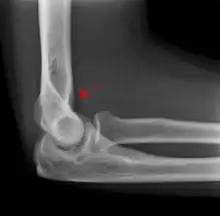

A subtle radial head fracture with associated positive sail sign

In children, a posterior fat pad sign suggests a condylar fracture of the humerus. In adults it suggests a radial head fracture.